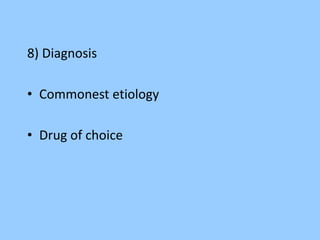

1. The document discusses EEG patterns and findings in various neurological conditions seen in children. It includes descriptions of normal EEG findings as well as abnormal patterns seen in conditions like absence seizures, West syndrome, benign childhood epilepsy with centrotemporal spikes, Lennox-Gastaut syndrome, non-convulsive status epilepticus, subacute sclerosing panencephalitis, and herpes encephalitis.

2. Case studies are presented with clinical histories and EEG findings to illustrate different pathologies. Treatment options are also mentioned for many of the conditions.